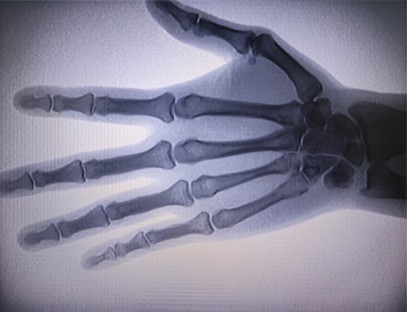

التخصص:تم تصميمه لتلبية احتياجات العيادات العظمية، ومناسب بشكل خاص لـالتصوير بالأشعة السينيةمن الأطراف مثل اليدين والمعصمين والمرفقين والكتفين والركبتين والكاحلين وما إلى ذلك.

تصوير واضح:يتم استخدام تكنولوجيا التصوير الرقمي المتقدمة لتوفير صور الأشعة السينية عالية الجودة، مما يساعد الأطباء على تشخيص الحالة بدقة.